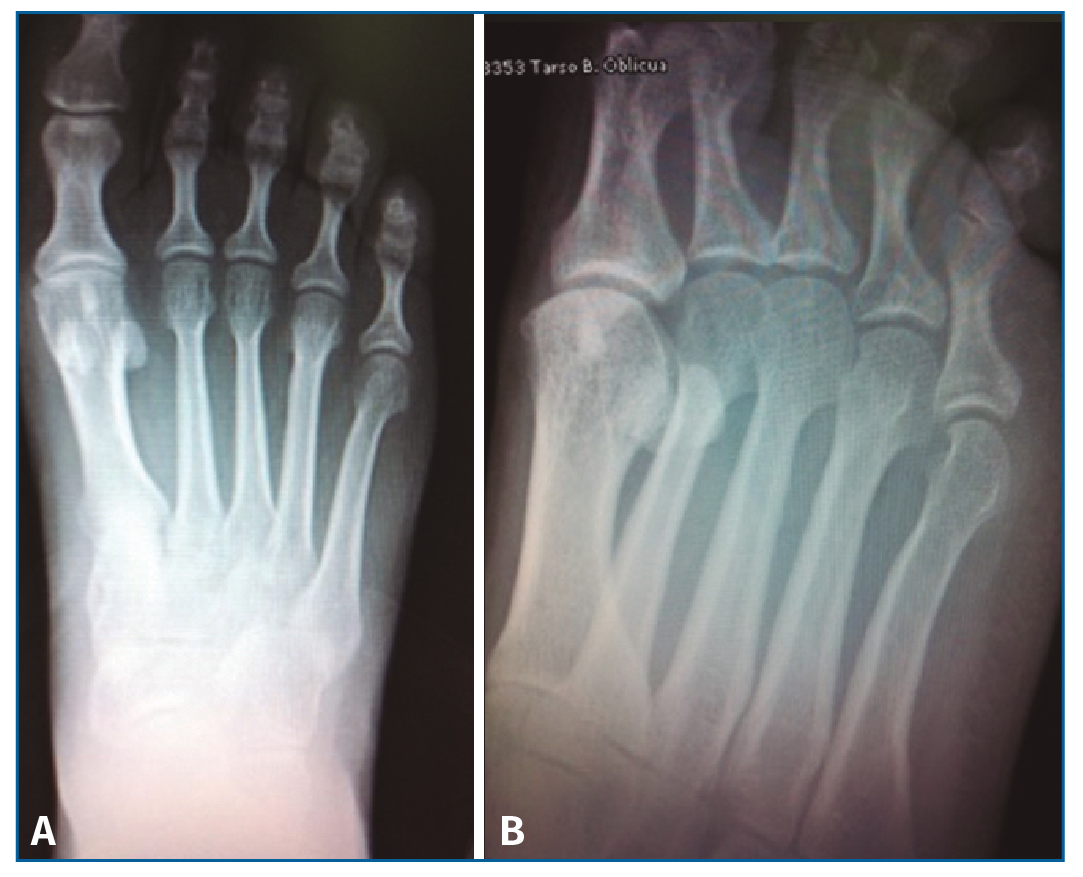

El estudio radiográfico en carga no mostraba alteraciones en la fórmula metatarsal ni lesiones óseas (Figura 1).

Figura 1. Radiología simple anteroposterior en carga (A) y oblicua antepié (B) sin lesiones óseas a nivel del 4.º metatarsiano.

El estudio radiológico en proyección anteroposterior y lateral en bipedestación, y oblicua del pie, debe ser la primera prueba complementaria solicitada(3)(4). En ella se determinará la longitud relativa de cada metatarsiano y la alineación frontal de las cabezas metatarsales.